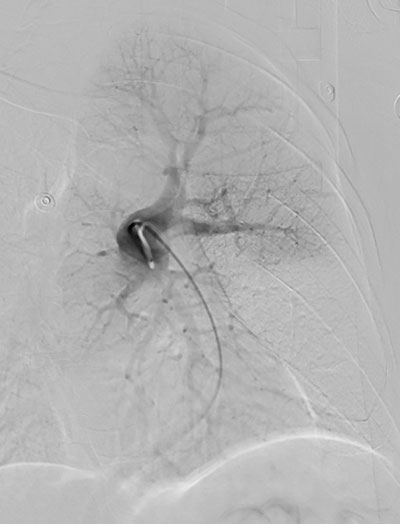

手术采用局麻的方式,经皮穿刺右股静脉,进入肺动脉造影后进一步明确诊断,左肺大面积肺栓塞。将鞘管到达左肺动脉后,应用Tendvia装置给予取栓,取出大量混合性血栓,取栓后左肺动脉血流完全恢复,血流分级达到Grade Ⅰ级,患者胸闷立即缓解。

左肺大面积肺栓塞

Tendvia取栓